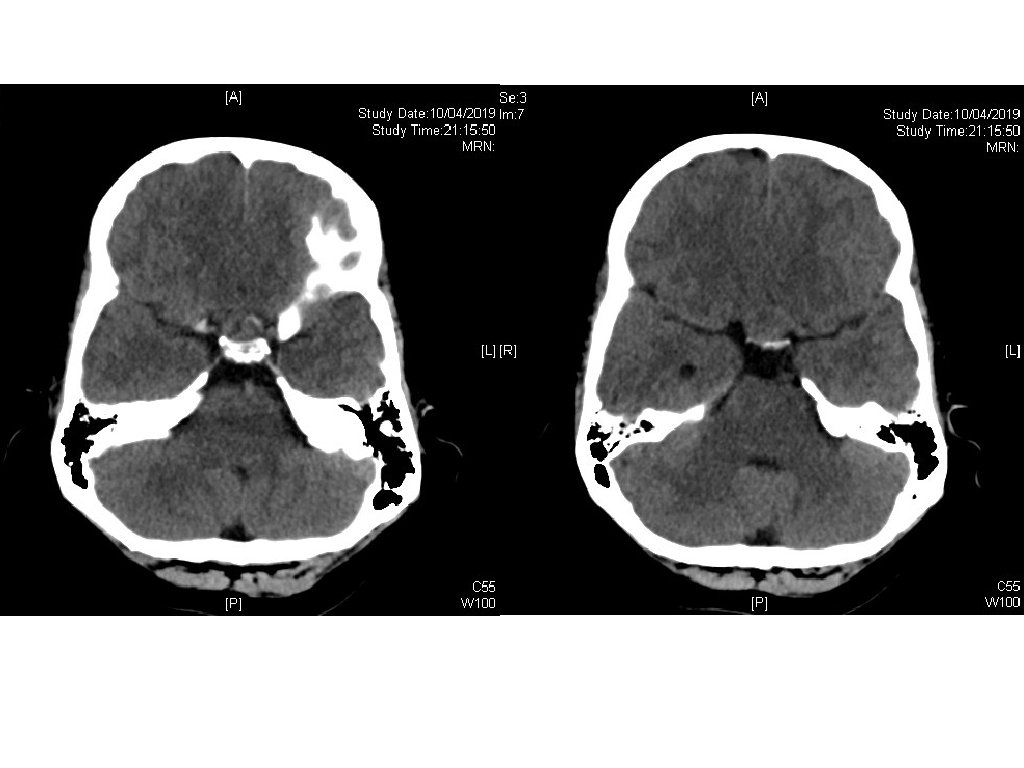

Case 1 • A 15 -year-old boy presented to Accident and Emergency Department with on and off headache for 2 months and intermittent nausea. • CT brain has been performed with 2 sections shown.

Case 1 - Questions 1. Describe the abnormality 2. What is the likely diagnosis? 3. What visual field problem the patient may experience? 4. What are the probable hormonal axis problems you need to look for? 5. What hormonal disease he may suffer after surgical excision of the lesion? 6. What is the probable diagnosis if the patient experiences polyuria and hypernatremia after surgical intervention?